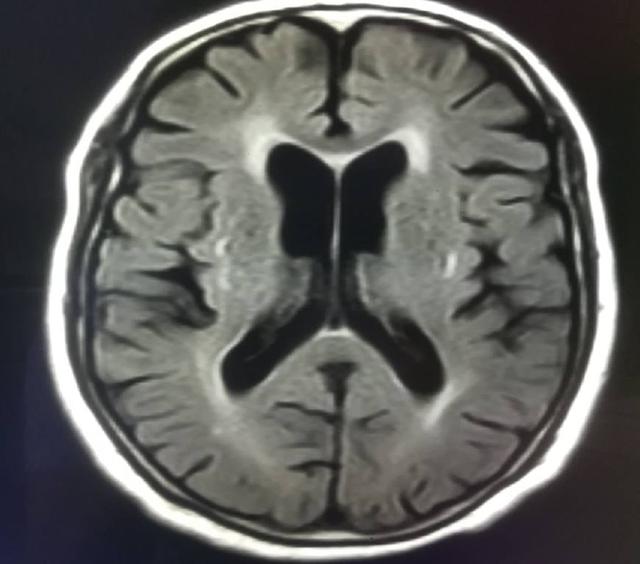

腦萎縮是指由各種原因?qū)е履X組織本身發(fā)生器質(zhì)性病變而產(chǎn)生萎縮的一種現(xiàn)象。病理上表現(xiàn)為腦組織體積縮小,細(xì)胞數(shù)目減少,腦室和蛛網(wǎng)膜下腔擴(kuò)大。本病多發(fā)生于50歲以上,病程可達(dá)數(shù)年至數(shù)十年,男性多于女性。

腦萎縮是一種影像描述,在做頭部ct的檢查時發(fā)現(xiàn)大腦體積以及皮質(zhì)范圍縮小、腦室、腦溝等位置變大的現(xiàn)象都被稱為腦萎縮。但是嚴(yán)格來說,腦萎縮不完全是臨床上的疾病,它只是形態(tài)學(xué)的變化。如果腦萎縮和神經(jīng)系統(tǒng)的功能發(fā)生異常結(jié)合,那它就是病變。